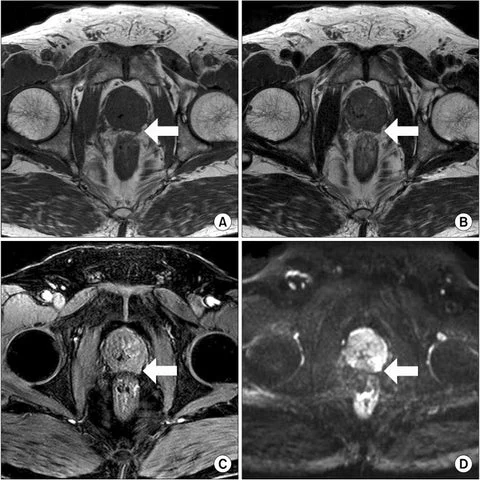

Olha só, minha próstata está saudável em apenas algumas semanas de uso! Meus exames que acabei de receber. Estou impressionado!!!